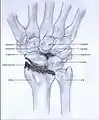

Stages

Post-traumatic osteoarthritis can be classified into four stages.[1][6] These stages are similar between SLAC and SNAC wrists. Each stage has a different treatment.

- Stage I: the osteoarthritis is only localized in the distal scaphoid and radial styloid.

- Stage II: the osteoarthritis is localized in the entire radioscaphoid joint.

- Stage III: the osteoarthritis is localized in the entire radioscaphoid joint with involvement of the capitolunate joint.

- Stage IV: the osteoarthritis is located in the entire radiocarpal joint and in the intercarpal joints. It also may involve the distal radio-ulnar joint (DRUJ).

Stage I

Stage II

Stage III

Stage IV